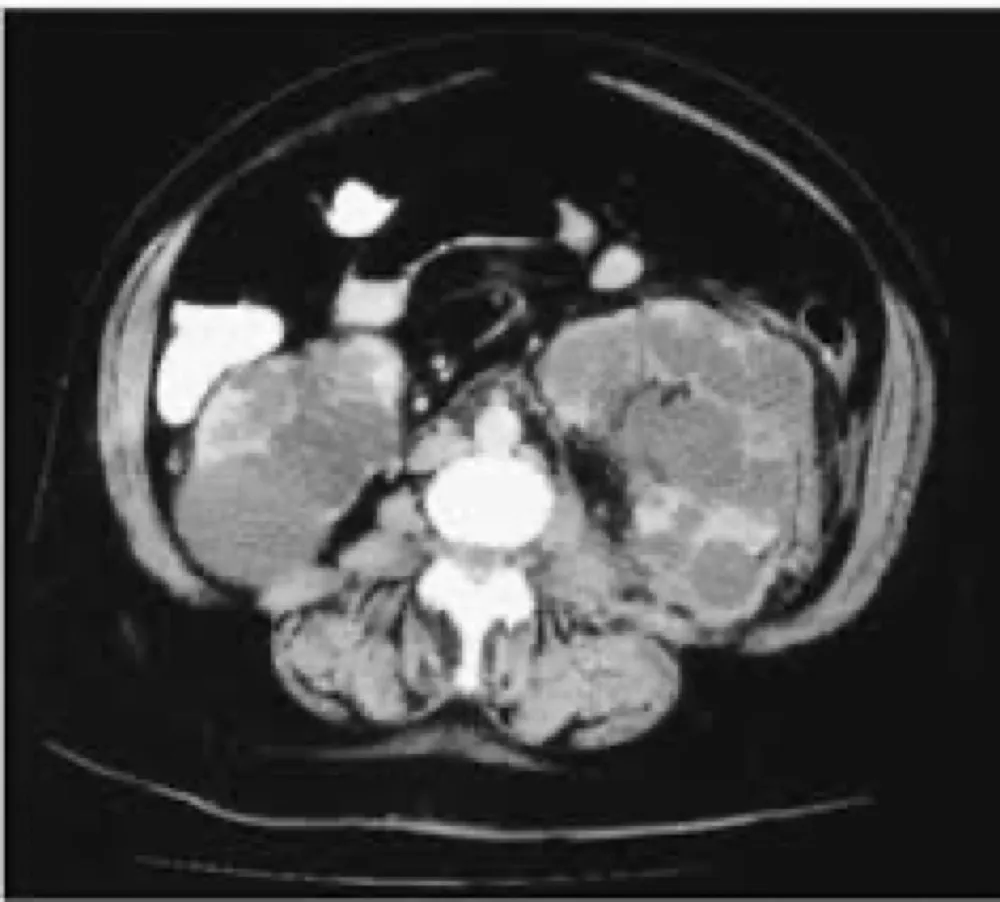

Doação renal em mulheres jovens pode impactar mais o feto do que a mãe — e esse dado muda o pré-operatório. O maior estudo já feito mostra aumento de PIG e sinais de disfunção placentária silenciosa, especialmente em nulíparas. Se você ainda não discute isso de forma explícita no consentimento, talvez esteja subestimando o risco.